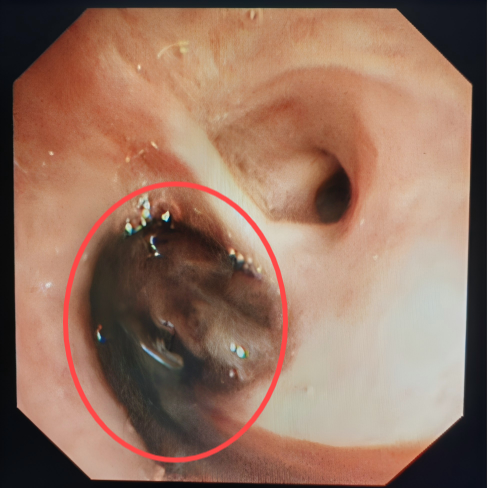

在实施支气管动脉栓塞术止血后,考虑到患者大量咯血后血液会阻塞气道,科室团队当即进行CT扫描,发现右肺已被凝血块完全阻塞,立即在床边通过气管镜清理气道内凝血块。术后,患者再无咯血,经住院治疗一段时间后,患者复查CT右肺基本恢复,顺利出院。

床边支气管镜清理凝血块

患者郑某某,因支气管扩张、空洞反复咯血十余年,再次复发后,咯血量明显增多,在当地治疗一周因效果不佳转入我院,就诊于急诊时仍咯血200ml,呼吸与危重症医学科立即启动绿色通道将患者送入介入室手术,术中仍持续咯血,在实施支气管动脉栓塞术后,患者咯血立即停止。在呼吸与危重症医学科医护人员的精心治疗下,患者最终好转出院,至今无复发。